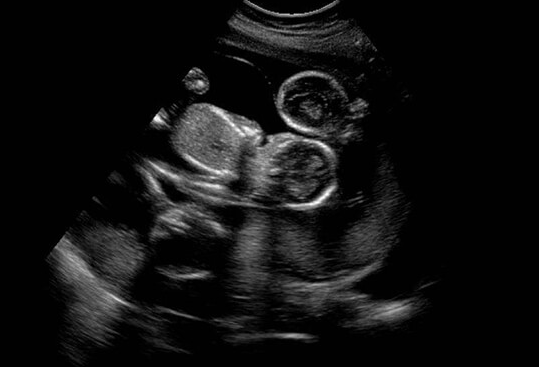

在吉尔吉斯斯坦德尔塔(DELTA)生殖医院,试管婴儿技术虽已达到国际先进水平,但仍有部分患者在移植一个月后未见胎心胎芽,这背后可能涉及多重因素。

实验室技术差异也可能影响胚胎质量。德尔塔医院配备先进的Time-lapse时差培养箱,可全程追踪胚胎发育潜力,但胚胎培养过程中仍可能受到温度、湿度、气体浓度等微小波动的影响,导致胚胎发育异常。